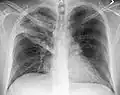

Normal AP CXR

Normal lateral CXR -

AP CXR showing left lower lobe pneumonia associated with a small left sided pleural effusion -

AP CXR showing right lower lobe pneumonia -

AP CXR showing pneumonia of the lingula of the left lung -

Right upper lobe pneumonia as marked by the circle. -

Left upper lobe pneumonia with a small pleural effusion.

Right lower lobe pneumonia as seen on a lateral CXR